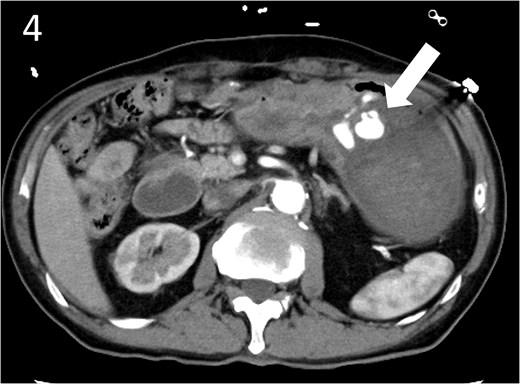

Contrast-enhanced computed tomography image showing active contrast extravasation in the stomach (arrow).